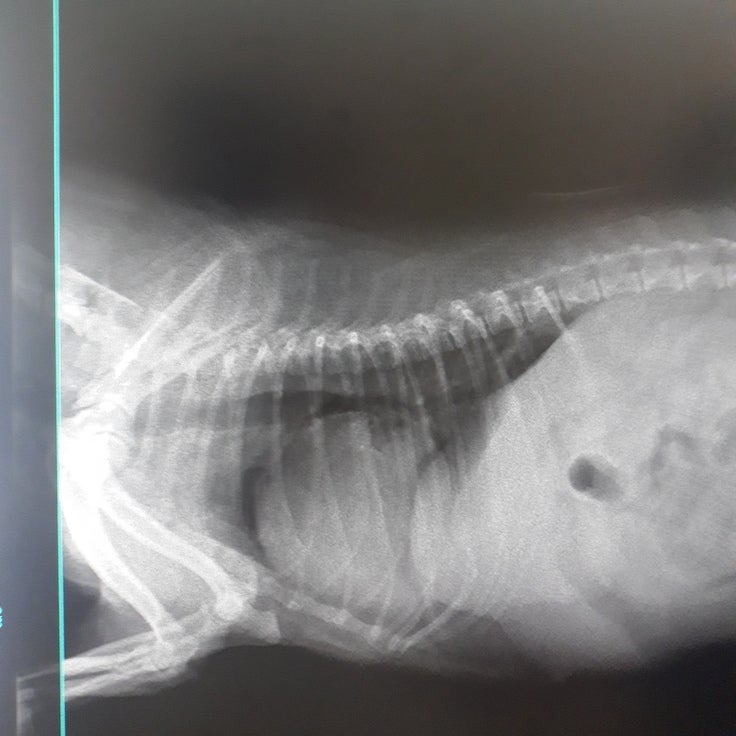

電話を切ってすぐに獣医師のところへ。B院で撮ったレントゲン、検査結果を元に

麻酔中に亡くなる可能性もあるし、合併症の可能性もある。でも助かる可能性もある。

通常の子宮はボーペンサイズの太さだそうです。

2020/10/06 15:04このサイトを上手く使いこなせなく申し訳ありません。先日子宮摘出手術後の子宮になります。全くの無知だったのですが、通常の子宮はボールペンサイズの太さということで、ここまで晴れてしまっておりました。心臓弁膜症や膵炎を併発していた中、無事に手術を終えることが出来ました。 もっと見る